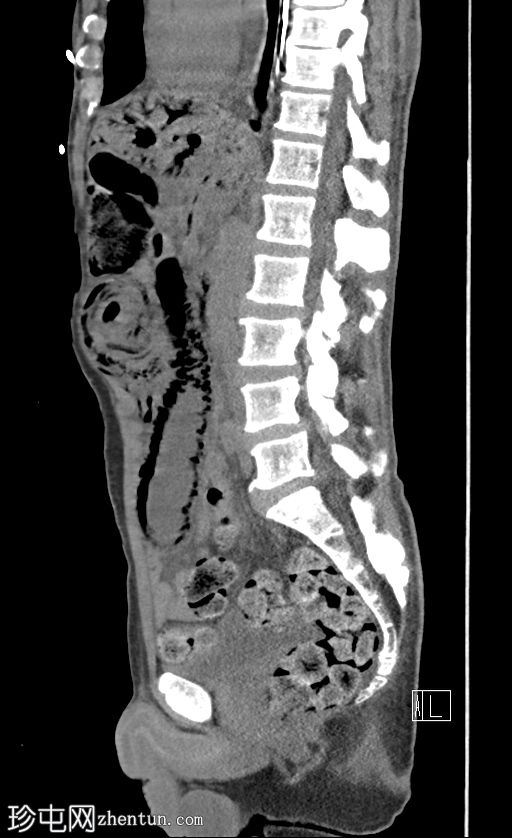

CT

7.jpg

矢状位片

平扫

门静脉积气。胃管末端位于胃底。下腹部可见长段小肠套叠,套叠起始点位于右下腹。伴有远端小肠广泛积气,左下腹肠段扩张,最符合小肠梗阻和缺血的表现,可能由长段小肠套叠引起。

病例讨论

门静脉积气通常预后不良,但该患者最终存活并出院。当肝脏内出现气体时,鉴别诊断包括胆道积气(胆道积气)和门静脉积气。通常区分并不困难:胆道积气聚集在肝脏中央,方向与胆汁流动方向一致;而门静脉积气则位于肝脏外周,方向与门静脉血流方向一致(由中央向外周)。